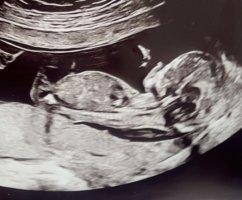

Spurte jordmor om kjønn og hun sa at det var lett å se at det var gutt. Jeg har en følelse på at det er en jente, og ble fortalt forrige gang at det var gutt også, men det viste seg å være jente.

Er det noen her som vet hvordan guttekjønn ser ut på ultralyd eller har bilde av det? Jeg husker hvordan det hun viste meg så ut, men for meg kunne det vært hva som helst

Ble fortalt på privat ultralyd mellom TUL og OUL at det var gutt sist gang, men på OUL fikk jeg vite at det var jente. Ble altså fortalt feil på samme tidspunkt forrige gang som det jeg er nå. Og så har jeg en følelse på jente igjen.